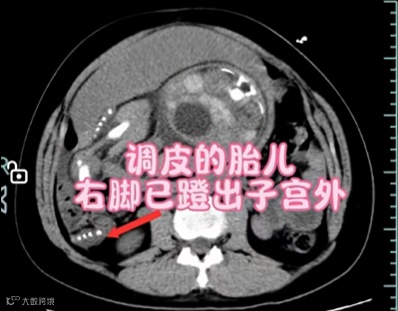

胎儿恰好一脚踢到了薄弱点,子宫破裂同时胎膜早破后羊水全流进了腹腔,胎儿的腿死死地卡住了这个破裂口让孕妈妈没有出现即刻的大出血,掩盖了破裂的症状,这也就解释了为什么小豆的羊水突然“人间蒸发”了,并且又腹痛不止,其实是她的身体在呼救。从锁定“子宫破裂”致命元凶,到新生儿响亮啼哭,医生用时18分钟托住了两条命。

还有网友调侃说:“魔童降世,好家伙”、“调皮的娃遇到了好的医生”,“惊心动魄,好在有惊无险”。